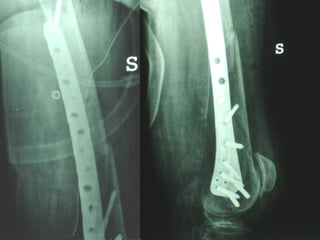

Dal Gennaio 2000 al Febbraio 2006 abbiamo trattato 167 fratture chiuse  con placca percutanea  in 164 pazienti :  27 lesioni diafisarie di gamba, 12 piloni tibiali ,  11 fratture prossimali di tibia, 36 fratture sovracondiloidee di femore, 17 fratture diafisarie di femore, 43 fratture metaepifisarie prossimali di omero, 21 diafisarie d’omero.  156 guarigioni 8 fallimenti

Dal Giugno 2002 al Dicembre 2004 abbiamo trattato 5 fratture esposte: 3 di tibia e 2 di ulna 5 guarigioni

I buoni risultati ottenuti dipendono da 5 punti fondamentali:   una accurata riduzione percutanea della frattura  precise vie di accesso  l’utilizzo della placca che consenta il più lungo braccio di leva possibile il pretensionamento della placca  una sintesi con un ridotto numero di viti

Precise vie di accesso

Placche lunghe e pretensionate

Placche lunghe e pretensionate Sintesi con un ridotto numero di viti